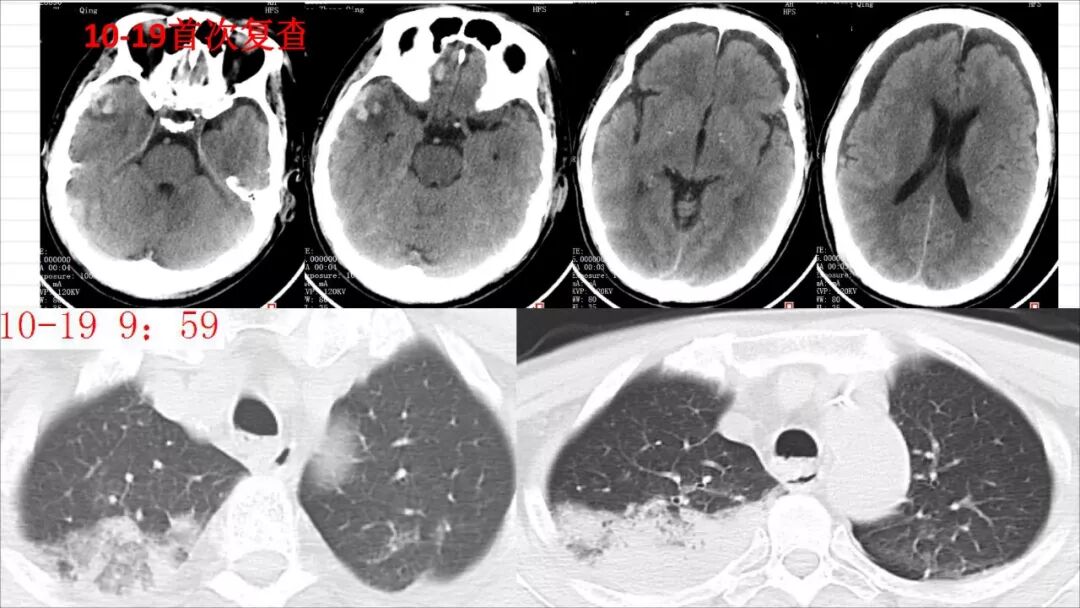

今天为大家分享的是《颅脑创伤-神经重症病例周刊》第113期,由株洲市三三一医院神经外科毛德龙医师带来的:老年病人慢性硬膜下血肿自然演变一例 ,天津医科大学总医院神经外科副主任兼NICU主任、“神外资讯中国颅脑创伤-神经重症专家组”委员江荣才教授对病例作出了精彩点评,欢迎观看、阅读。